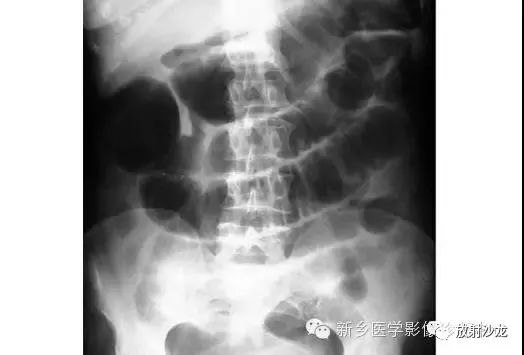

腹部脏器有实质器官和空腔脏器之分,其正常腹平片表现不同。

● 腹平片上实质器官的正常表现:

实质器官:肝、胰、脾和肾等是中等密度,但借助于器官周围或邻近的脂肪组织和相邻充气肠胃的对比,于腹平片上,可显示器官的轮廓、大小、形状及位置。

正位片在部分病人可显示肝下缘,肝下缘与肝外缘相交形成肝角,一般呈锐角。

脾上极与左膈影融合,下极较圆钝。而肾沿腰大肌上部排列。

胰腺于平片上不易显示。子宫偶尔显影,位于膀胱上缘上方呈扁圆形软组织影。

● 空腔脏器在腹平片上的主要表现:

空腔器官:膀胱的脏壁为中、胆囊和肠胃道等密度,依腔内容物不同而x线表现不同。

胃、十二指肠球部及结肠内可含气体,于腹平片上可显示其内腔。小肠除婴幼儿可有积气外,一般充满食糜及消化液,与肠壁同属中等密度,因缺乏对比而不能显示。

如胃内有较多固态食物,结肠或直肠内有较多粪便,由于它们周围有气体衬托,故可显出软组织密度斑片或团块影。

结肠分布于腹部四周。膀胱和胆囊周围有较多脂肪,也可显示部分边缘。